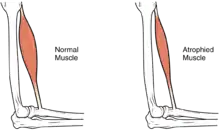

In the long term, the loss of muscle function can have additional effects from disuse, including atrophy of the muscle. Immobility can lead to pressure sores, particularly in bony areas, requiring precautions such as extra cushioning and turning in bed every two hours (in the acute setting) to relieve pressure.[49] In the long term, people in wheelchairs must shift periodically to relieve pressure.[50] Another complication is pain, including nociceptive pain (indication of potential or actual tissue damage) and neuropathic pain, when nerves affected by damage convey erroneous pain signals in the absence of noxious stimuli.[51] Spasticity, the uncontrollable tensing of muscles below the level of injury, occurs in 65–78% of chronic SCI.[52] It results from lack of input from the brain that quells muscle responses to stretch reflexes.[53] It can be treated with drugs and physical therapy.[53] Spasticity increases the risk of contractures (shortening of muscles, tendons, or ligaments that result from lack of use of a limb); this problem can be prevented by moving the limb through its full range of motion multiple times a day.[54] Another problem lack of mobility can cause is loss of bone density and changes in bone structure.[55][56] Loss of bone density (bone demineralization), thought to be due to lack of input from weakened or paralysed muscles, can increase the risk of fractures.[57] Conversely, a poorly understood phenomenon is the overgrowth of bone tissue in soft tissue areas, called heterotopic ossification.[58] It occurs below the level of injury, possibly as a result of inflammation, and happens to a clinically significant extent in 27% of people.[58]

Muscle mass is reduced as muscles atrophy with disuse.